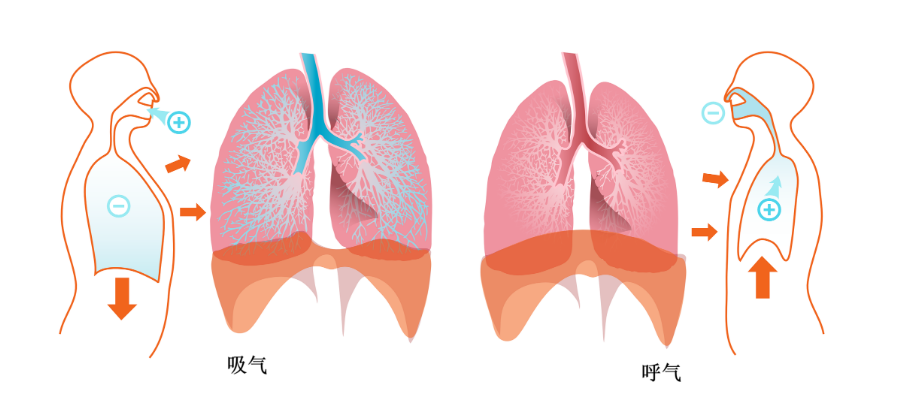

我们的呼吸(xī)运(yùn)动是由呼吸(xī)肌(jī)收缩舒张(zhāng)引(yǐn)起的胸廓扩大与(yǔ)缩小(xiǎo)的变化,当呼吸(xī)功能出现问题时,会(huì)使新鲜空气进入肺部的比重减(jiǎn)少,导致(zhì)身(shēn)体内器官的无法顺利运作与代谢,使得身体(tǐ)出现(xiàn)各种(zhǒng)问题。

呼吸(xī)肌(jī)训练是(shì)一种力(lì)量训练,其利用呼吸肌的可塑造(zào)性,通过在吸气或(huò)呼气过程中施加(jiā)阻(zǔ)力,呼吸肌(jī)克(kè)服阻力做功,以提高肌力达到肺康复目的。